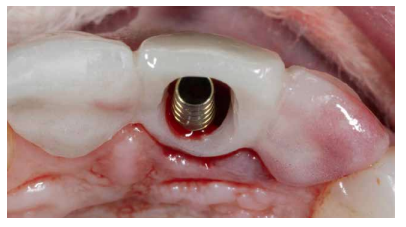

Se colocó el IOI (Neo AlphaBio Medical10® 3,25mm x 11mm). Éste fue ubicado a una profundidad respecto al futuro margen gingival que se precisaba conseguir de 4 mm de distancia respecto al hombro del IOI. En este caso, el margen gingival de referencia fue el del propio ICSI, ya que se encontraba intacto y sin modificaciones, mientras que en el caso del ICSD, existía una recesión gingival de 2 mm. En este proceso se tuvo en consideración la elección de un diámetro del IOI que permitiera obtener un espacio o “gap” que facilitara la reconstrucción de la cortical ósea vestibular, prestando especial atención al fenotipo gingival, con el fin de permitir también el manejo de los tejidos blandos (Figuras 7A y 7B).

Se obtuvo estabilidad primaria, logrando anclaje en el hueso residual palatino a un torque de inserción de 35 N/cm2 . Posteriormente, se procedió a la colocación de un pilar temporal protésico.